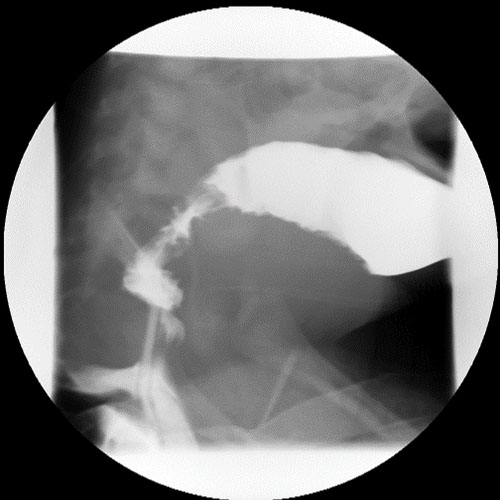

Under fluoroscopic guidance, the rectum and colon were filled with contrast, and fluoroscopic images were obtained.

The colon was filled through its entire length, confirmed by contrast filling of the appendix and reflux into terminal ileum.

There are ulcerations/mucosal abnormality.

There is a fistula.